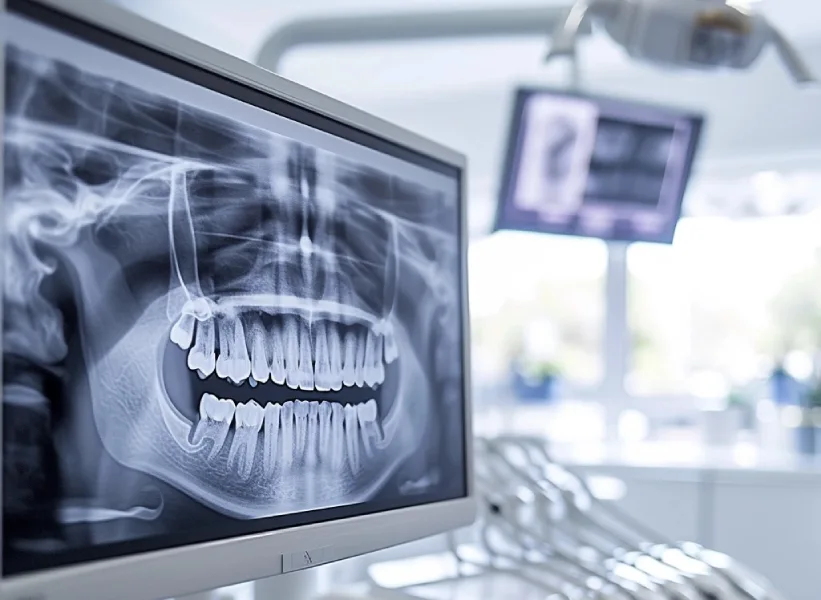

Рентгенодиагностика в стоматологии

С открытием в 1895 году рентгеновских лучей у медиков появилась возможность получить картинку скрытых от внешнего наблюдения органов. На компьютере или на светочувствительной пластинке после облучения исследуемого органа мягкие ткани выглядят светло-серыми, кости – серыми, а коронки, пломбы и импланты – белыми. Зоны воспаления смотрятся как черные пятна. Методы рентгенодиагностики постоянно совершенствуются. Рентген сегодня стал обыденной процедурой при обращении к стоматологу. И это совершенно обосновано, так как позволяет с минимальными рисками быстро получить желаемый результат.

ОРТОПАНТОГРАММА. Это современный метод рентгенодиагностики, позволяющий врачу увидеть развернутую панорамную картину зубных рядов, представленную в одной плоскости. Для съемки используется специальный прибор пантомограф. Он согласованно перемещает вокруг головы пациента рентгеновский излучатель и кассету с пленкой или датчик рентгеновского излучения. В результате на снимке получается плоское изображение изогнутого объекта (челюсти или черепа). Пантомограф может быть пленочным или цифровым, работающим вместе с компьютером.

3Д КТ РЕНТГЕН — самый продвинутый метод рентгенодиагностики. Позволяет увидеть проблемный объект со всех сторон. Естественно, применяется совместно с компьютером. Незаменим перед проведением имплантации. Назначается врачом перед ортодонтическим лечением, костной пластикой или имплантацией, а также в ряде других случаев. Дает четкую картинку сложившейся ситуации, не представляет опасности для пациента из-за чрезвычайно низкой дозы получаемого им облучения. Именно снимок КТ используется в 3Д цифровом планировании.